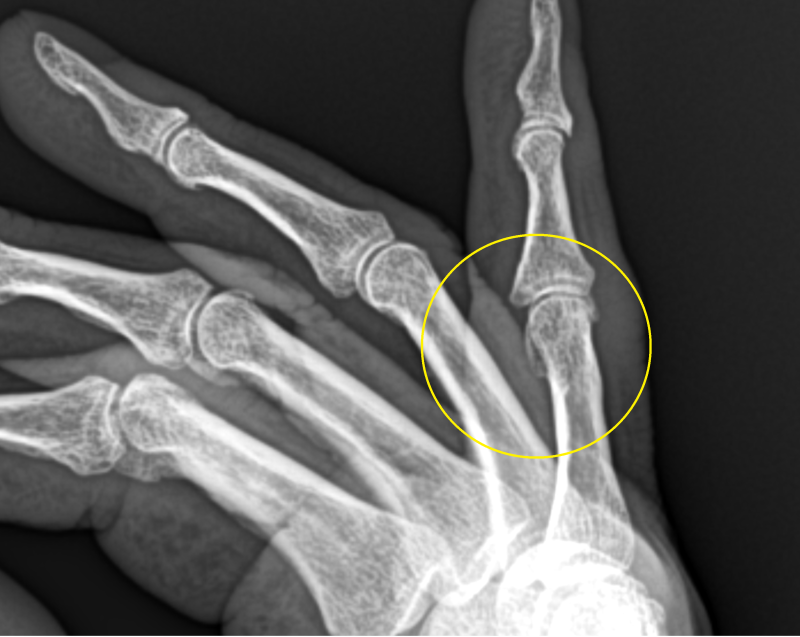

손가락 석회[석회성 건염]

먼저 오자마자 초음파를 봤어요 석회의 크기가 전과 별 차이가 없네요.다시 한번 제대로 치료를 하기로 했어요.-치료방법-1.주사요법2.충격파3.석회흡입술